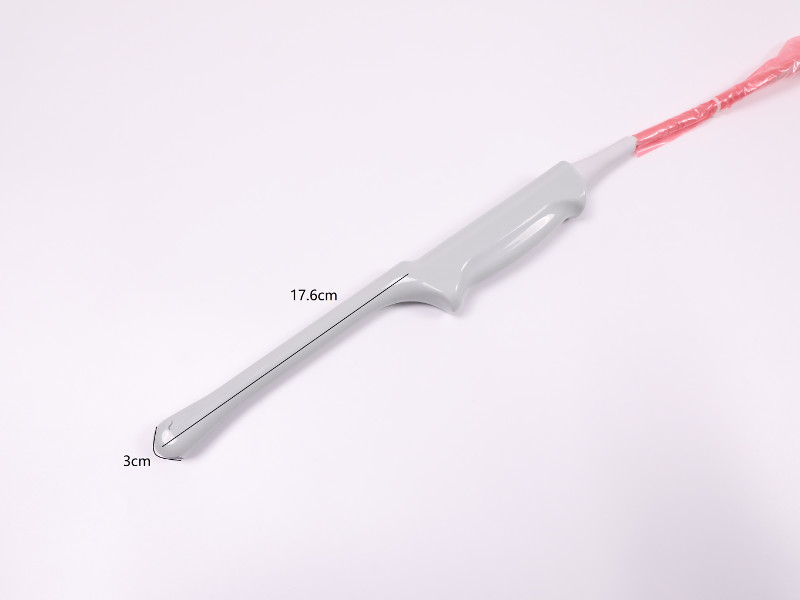

- A transvaginal head - 1 piece

- application: obstetrics / gynecology, prostate

- harmonic frequency: 3.2, 3.6, 4.0, 5.0 MHz

- base frequency: 5.0, 6.5, 10.0 MHz

- depth range: 20 ~ 280mm

- TP10 transvaginal head